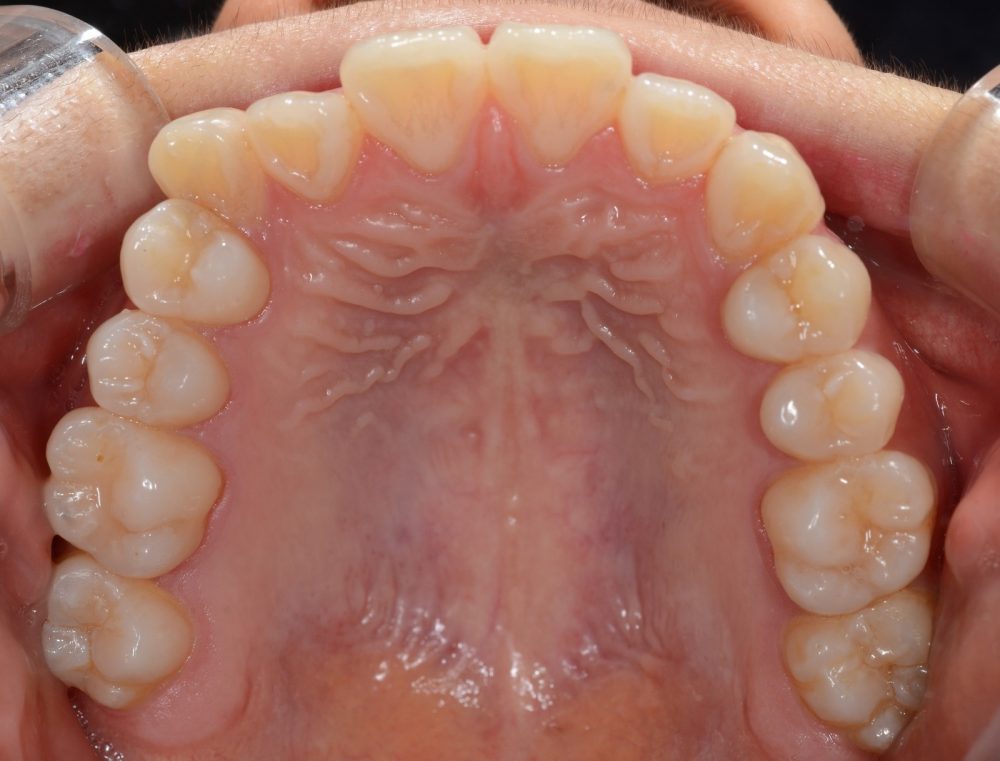

Case study 2

Before